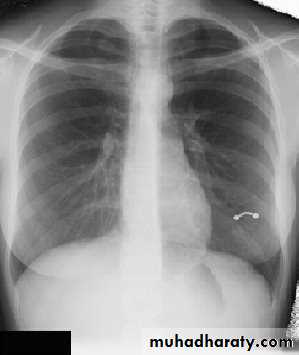

Pleural Effusion on Chest Radiographs.

Posteroanterior (A) and lateral (B) chest radiographs demonstrate the typical meniscoid appearance (arrows) in a patient with a left pleural effusion